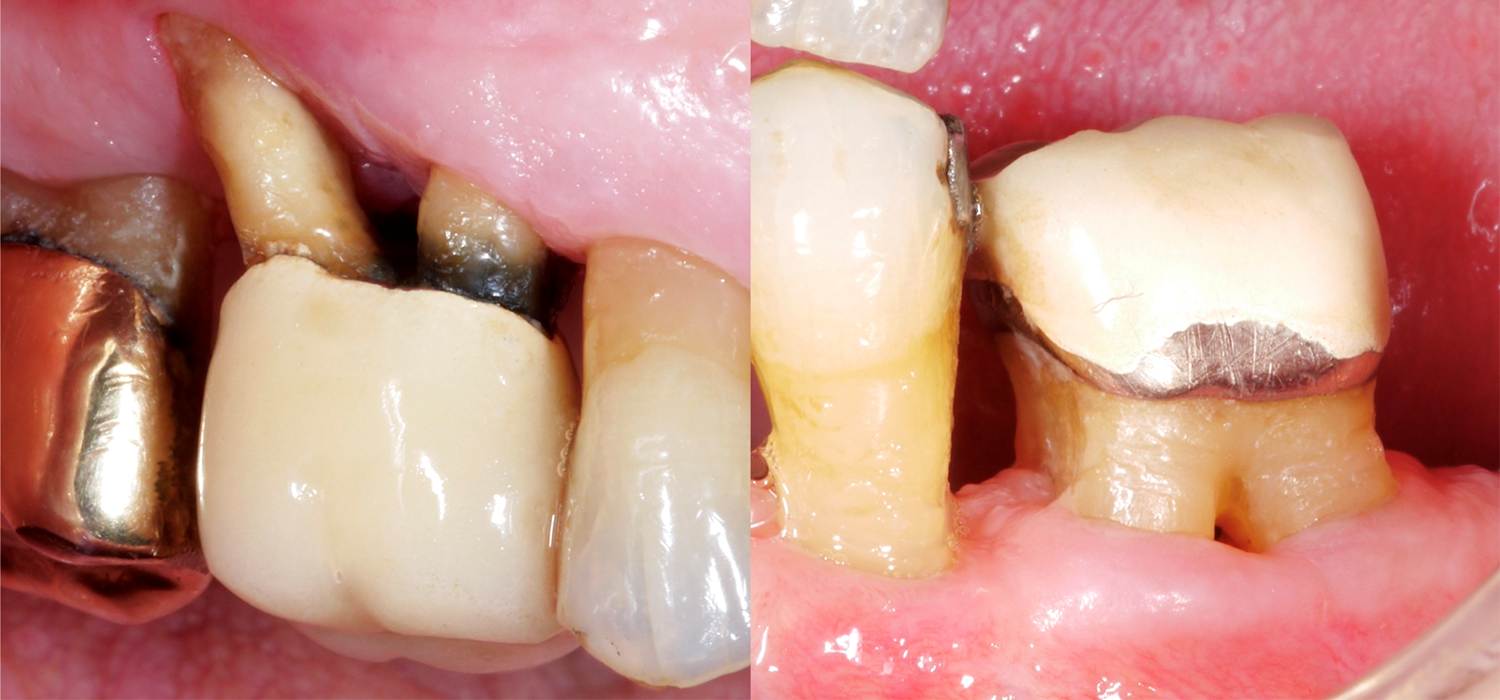

Wenn man nun an die Zähne denkt, dann sind natürlich mehrwurzelige Zähne oft viel schwieriger zu therapieren, im Speziellen, wenn sie einen Furkationsbefall aufweisen. Warum ist der Furkationsbereich so anspruchsvoll? Der Zugang für die mechanische Reinigung der Wurzeloberfläche ist im Vergleich zu einwurzeligen Zähnen viel schwieriger, der Furkationseingang kann oft sehr klein/schmal sein, und zusätzlich kann es noch anatomische Besonderheiten, wie beispielsweise Schmelzprojektionen, geben.

In einer kürzlich publizierten Arbeit aus Frankfurt (Eickholz 2021) wurden im Speziellen Zähne mit einem durchgängigen Furkationsbefall untersucht. Sie untersuchten insgesamt 265 Zähne mit einem durchgängigen Furkationsbefall von 160 PatientInnen; alle PatientInnen waren seit mindestens 5 Jahre in parodontaler Erhaltungstherapie. Folgende wichtige Punkte sollten wir basierend auf diesen Daten berücksichtigen: